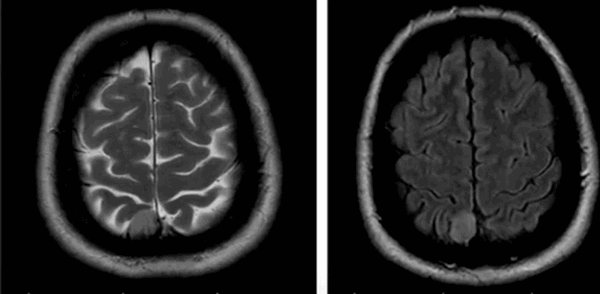

Множественные метастазы в вещество головного мозга на МРТ без контраста

Вторичными проявлениями патологии могут быть:

- латеральная дислокация срединных структур;

- смещение сосудистого пучка;

- изменение величины и деформации желудочков;

- аксиальная дислокация;

- окклюзионная гидроцефалия при блокаде ликворных путей;

- смещение или деформация базальных цистерн;

- отек мозга в зоне опухоли и вокруг нее (локальный, генерализованный, тотальный, перивентрикулярный).